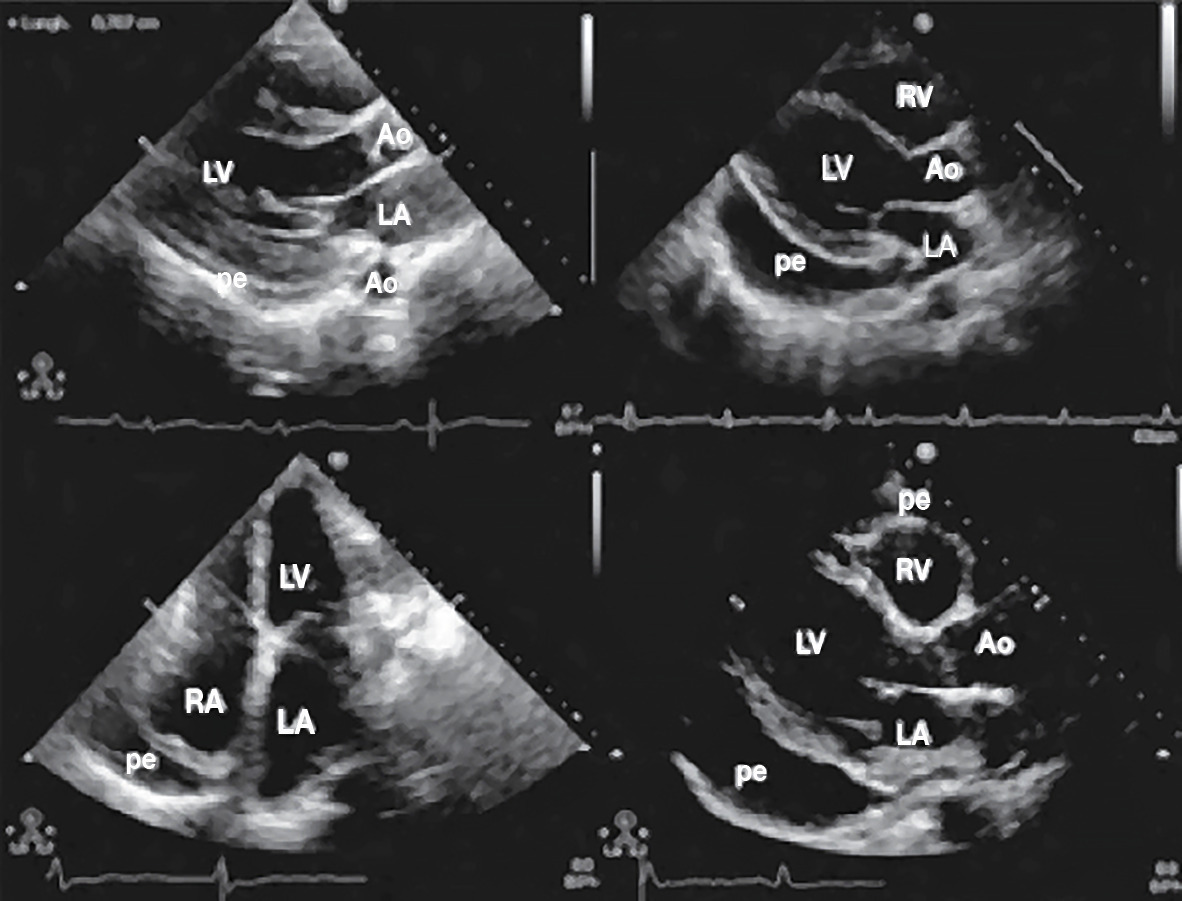

L’échocardiographie révèle le décol- lement des 2 feuillets du péricarde, avec un espace vide d’écho en avant ou en arrière du myocarde (fig. 1 ) ; elle précise son abondance et sa tolérance et permet de suivre l’évolution.

L’échocardiographie révèle le décol- lement des 2 feuillets du péricarde, avec un espace vide d’écho en avant ou en arrière du myocarde (